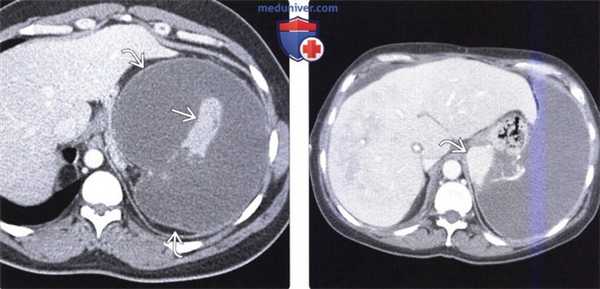

(Слева) На аксиальной КТ с контрастным усилением у пациента, страдающего серповидноклеточной болезнью, определяется увеличение селезенки с наличием в ее структуре множественных клиновидных инфарктных участков. На начальных этапах серповидноклеточной болезни может определяться только спленомегалия, затем возможны аутоинфаркт и обызвествление селезенки.

(Справа) На аксиальной КТ с контрастом определяется тотальный инфаркт селезенки с наличием лишь минимального количества ее паренхимы, накапливающего контраст. Обратите внимание на периферическое контрастное усиление органа (симптом «ободка») по краю зоны инфаркта, обусловленное сохраненным кровообращением в сосудах капсулы селезенки. (Слева) На аксиальной КТ с контрастным усилением у мужчины 67 лет с данными о фибрилляции предсердий в анамнезе на протяжении 10 лет, у которого на данный момент возникла боль вверху живота слева, определяется инфаркт селезенки в виде периферически расположенного гиподенсного участка с четкими краями.

(Справа) На аксиальной КТ с контрастным усилением у этого же пациента визуализируется тромб в левом желудочке, который стал причиной эмболии артериального сосуда селезенки. Эмболия у пожилых пациентов является наиболее частой причиной инфаркта селезенки.